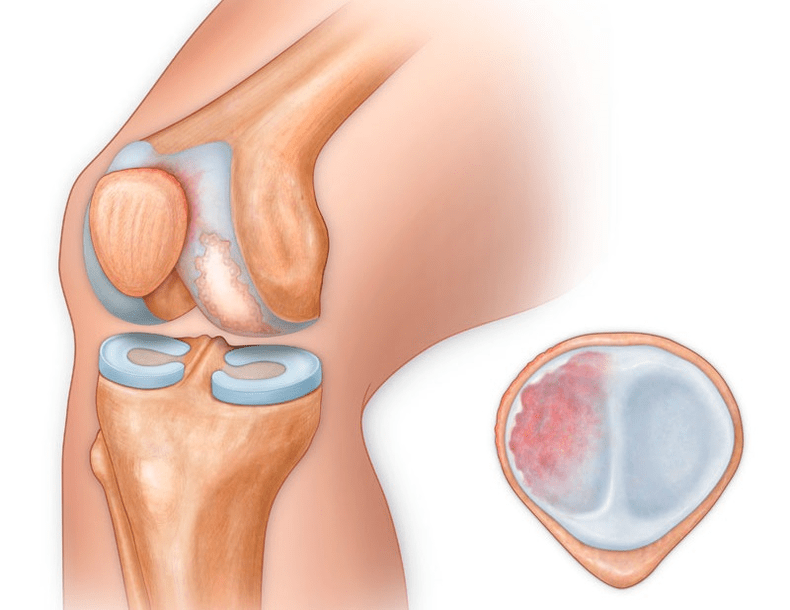

Be vidinės ar išorinės kelio dalies, artrozė gali pažeisti ir paviršius tarp girnelės ir šlaunikaulio tarpkondilinio griovelio. Ši parinktis vadinama patellofemoralinė artrozė.

Jos priežastis dažniausiai yra girnelės subluksacija, lūžis arba šoninis iškrypimas.

Kelio sąnario artrozė (gonartrozė) yra progresuojanti lėtinė kelio sąnarių liga, pasireiškianti jo kremzlinės dalies (šlaunikaulio ir blauzdikaulio sąnarinių paviršių) pažeidimu, suplonėjimu ir sunaikinimu, taip pat subchondralinio kaulo pažeidimu. Tyrimais (artroskopija ir magnetinio rezonanso tomografija) įrodyta, kad procese, be sąnario kremzlės pažeidimo, dalyvauja meniskai ir sinovinė membrana. Gonartrozė yra viena iš labiausiai paplitusių ortopedinių patologijų. Yra jos sinonimai – osteoartritas (OA), deformuojantis artrozė. Liga yra svarbi socialinė-ekonominė problema, nes yra plačiai paplitusi ir dėl nuolatinio skausmo smarkiai pablogina pacientų gyvenimo kokybę, be to, tampa didelės neįgalumo priežastimi.